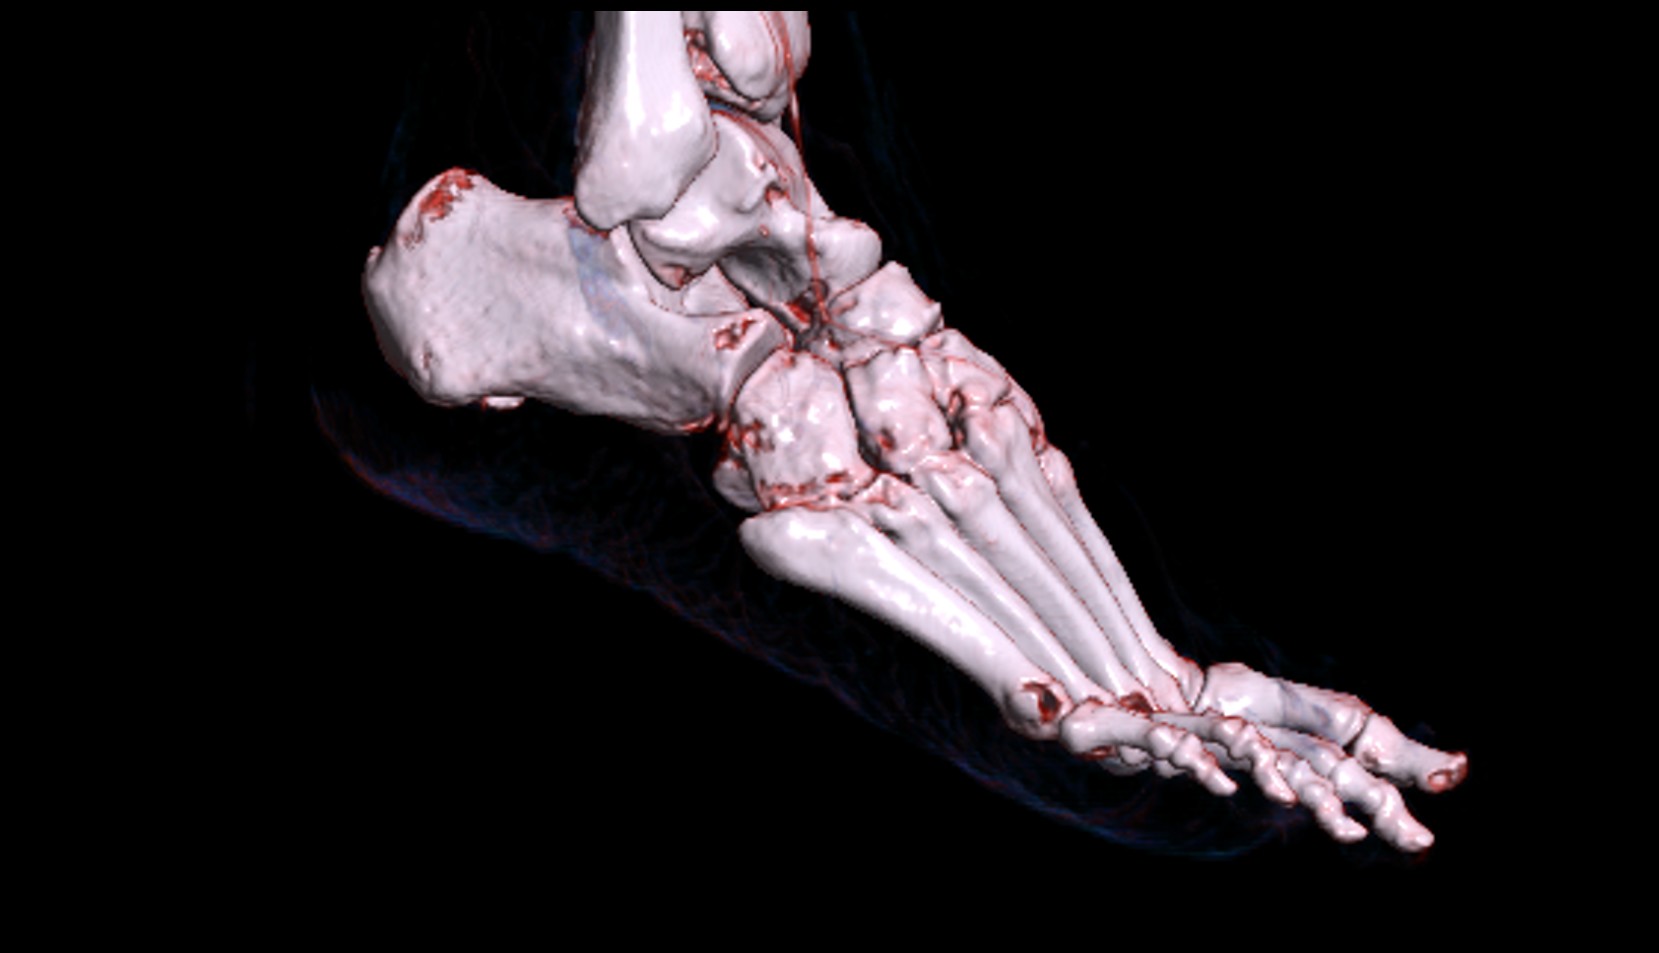

- Talus

- Head of talus

- Body of talus

- Neck of talus

- Calcaneus

- Anterior process of calcaneus

- Sustentaculum tali

- Cuboid

- Ankle joint

- Talocalcaneal joint

- Talocalcaneonavicular joint

- Calcaneocuboid joint